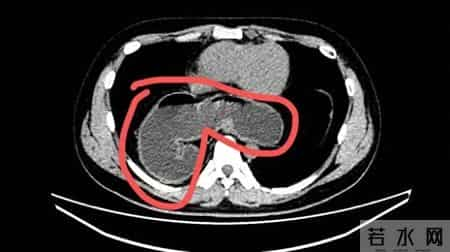

直到去年10月,因为反复咳嗽不止并出现迁延不愈的肺炎,林先生在当地医院就诊,肺部CT检查中发现:一部分的胃竟然“跑”进了胸腔里!

影像资料显示,小伙子的部分胃通过食管裂孔疝“逃跑”至胸腔。